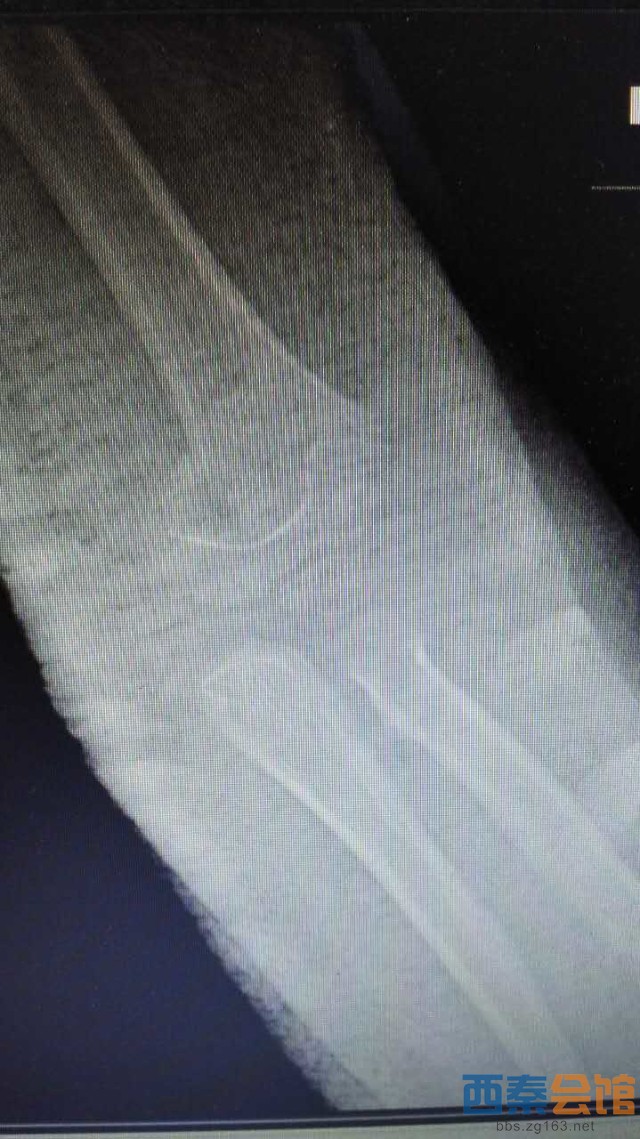

肱骨髁上骨折为儿童常见病,往往需要手术治疗,常规手术为做肘关节内外侧切口,交叉克氏针固定,手术创伤大,伤口瘢痕长,不美观等问题。市三医院骨一科梁涛主任根据患者需求,新引进儿童肱骨髁上骨折前路手术,仅3cm小切口切开复位后,于肱骨内外髁闭合穿针内固定,伤口皮内缝合,不需要拆线,术后伤口愈合快,术后4周可去除石膏托锻炼,术后6周可拔出克氏针,具有创伤小、美观、患者护理方便等优点。目前该5岁患者恢复良好,已出院休养。